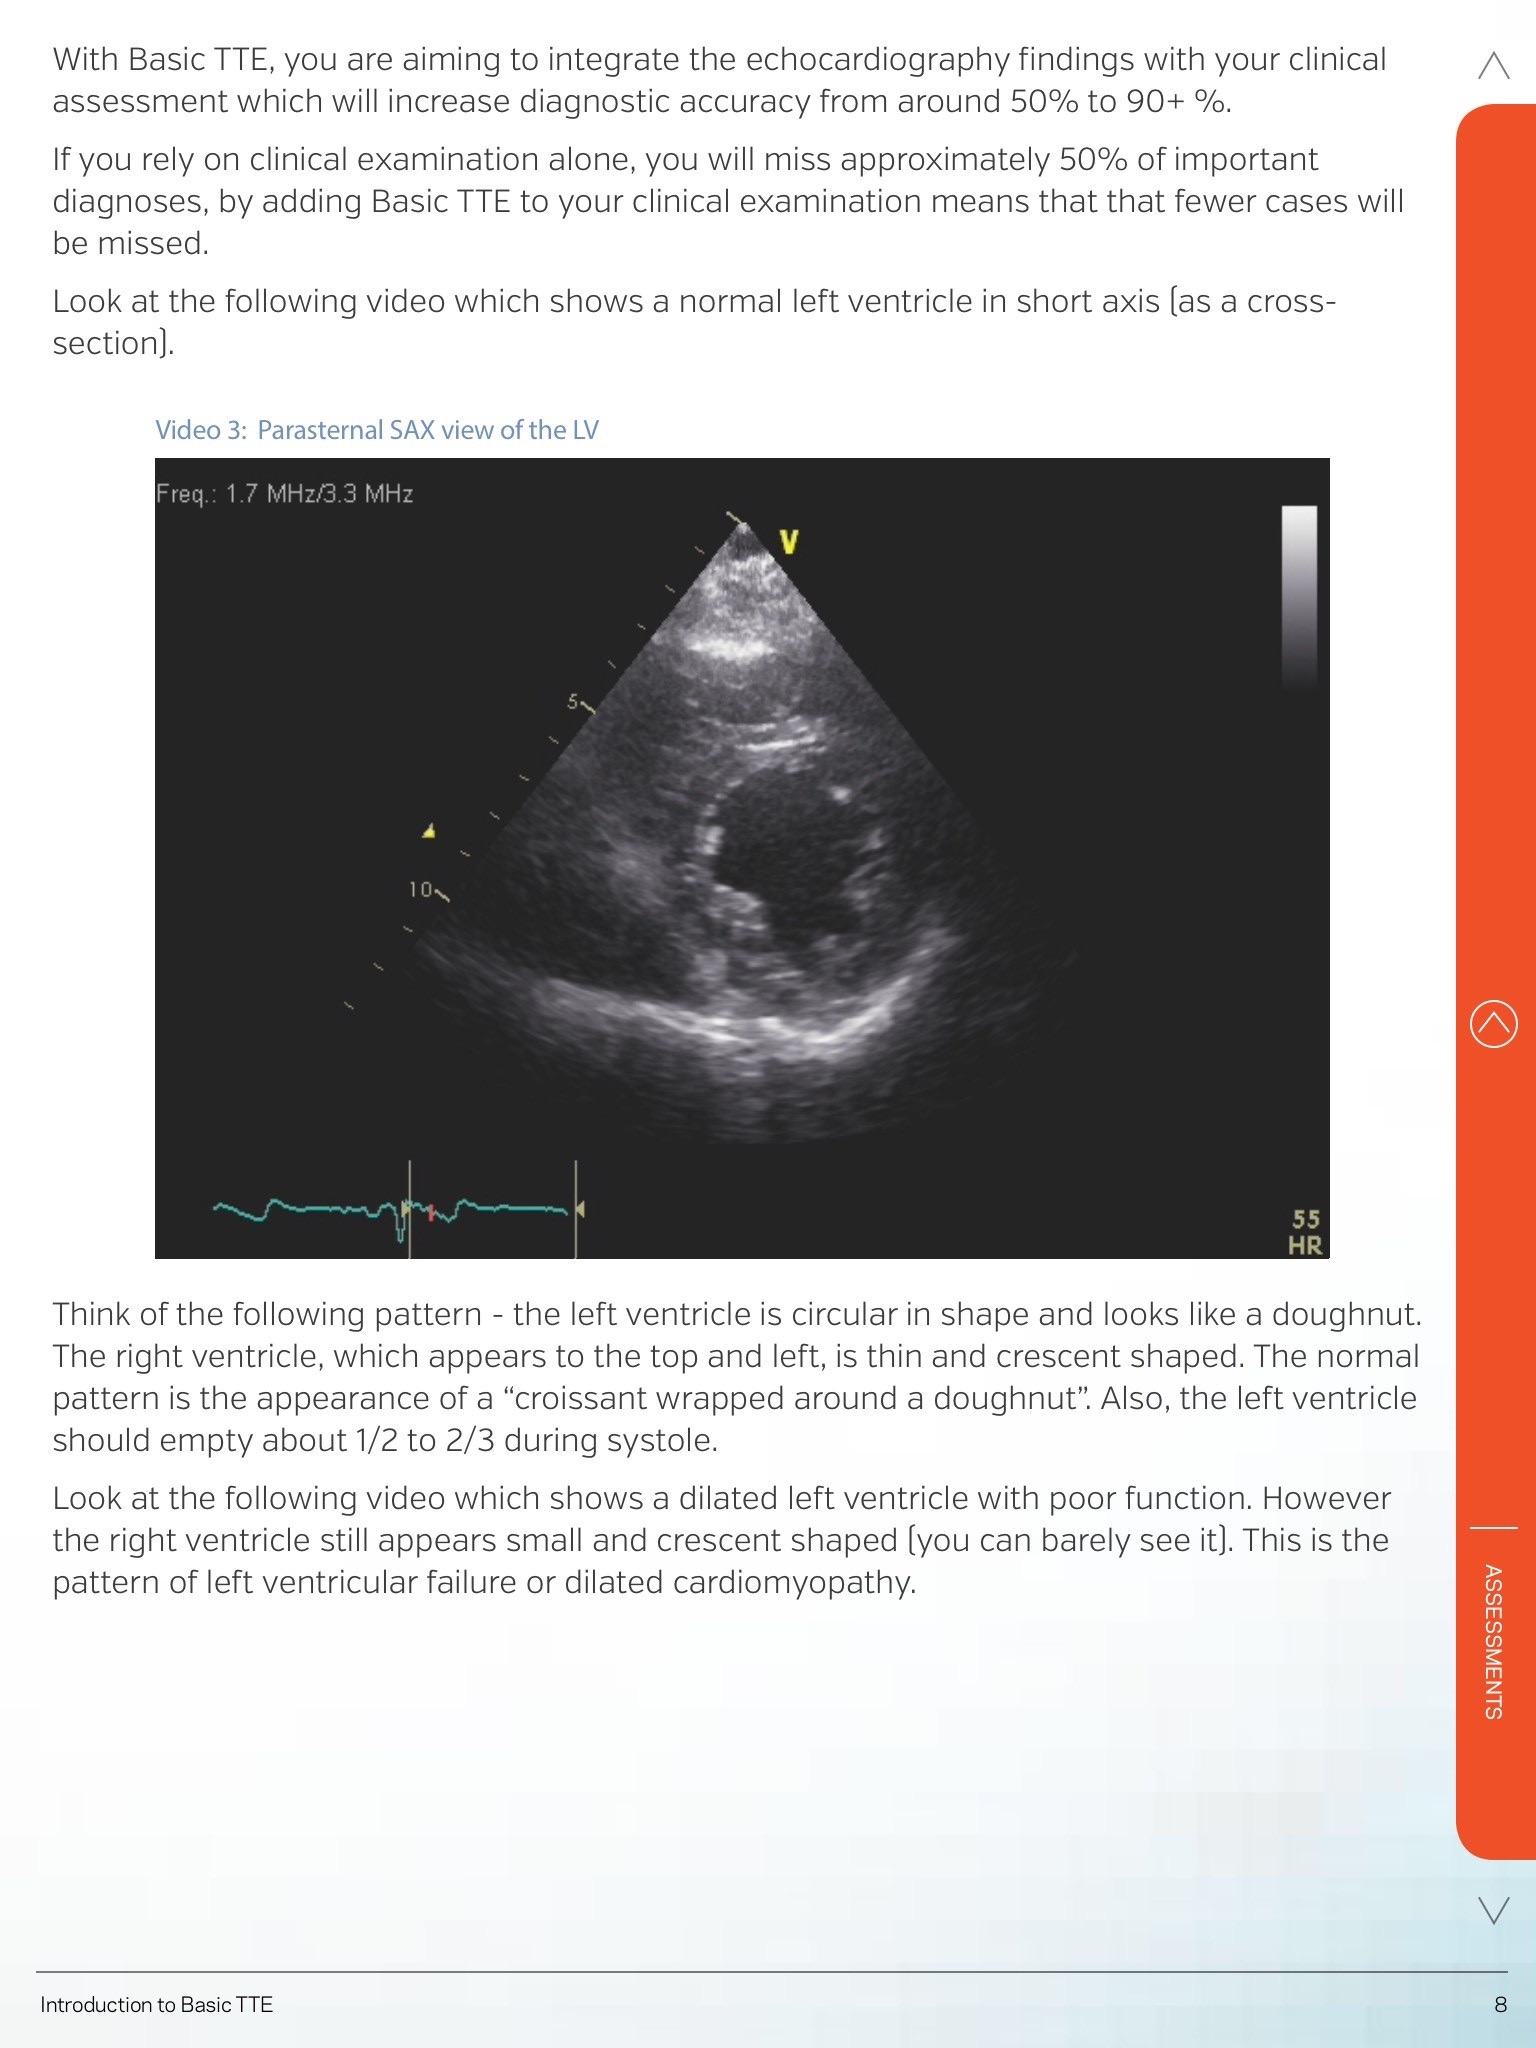

The Heartweb app has been designed to deliver custom online education courses. Our courses teach clinical ultrasound and echocardiography to health professionals worldwide. The app will allow students to read their course materials via a tablet. The e-learning courses allow the student the flexibility to study in their own time and place. Existing students will log into the app and will be able to gain access to the relevant course materials. Content within the HeartWeb app is proprietary curriculum material for and only available to enrolled students. Heartweb Pty Ltd is an established, international, commercial provider of online higher education.